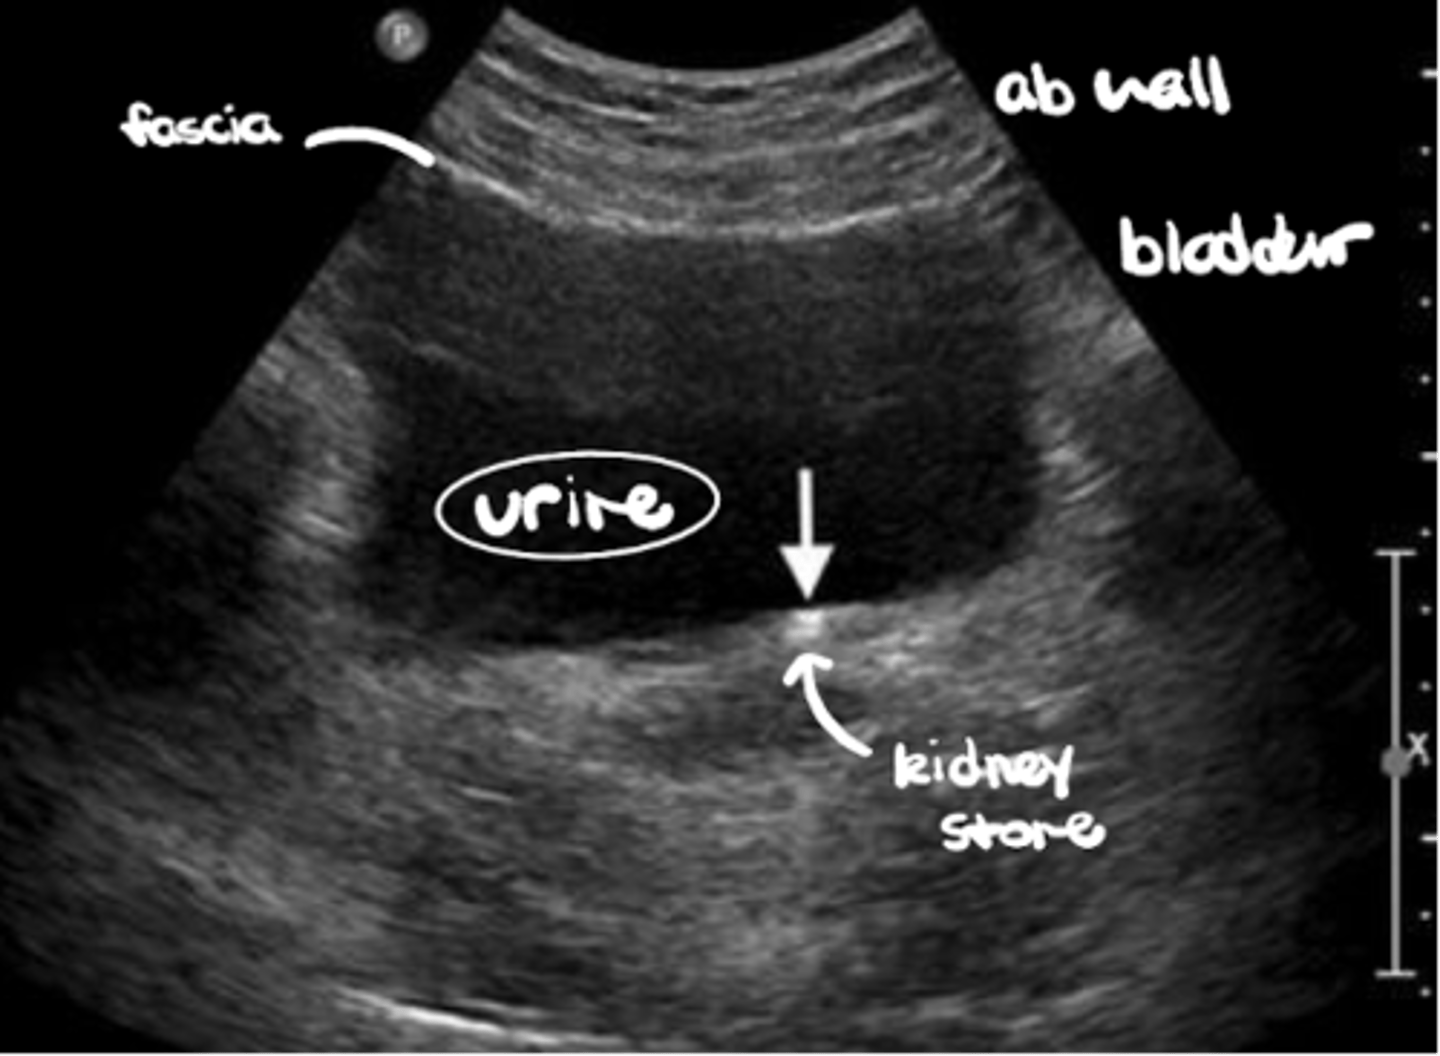

The abdominal wall is _______-echoic vs. the _______-echoic urine

Hyper-echoic abdominal wall vs. anechoic urine

The fascial wall is _______-echoic vs. the _______-echoic abdominal muscles

Hyper-echoic fascial wall vs. hypo-echoic abdominal muscles

The a kidney stone is _______-echoic vs. the _______-echoic abdominal wall

Hyper-echoic kidney stone vs. hypo-echoic abdominal wall